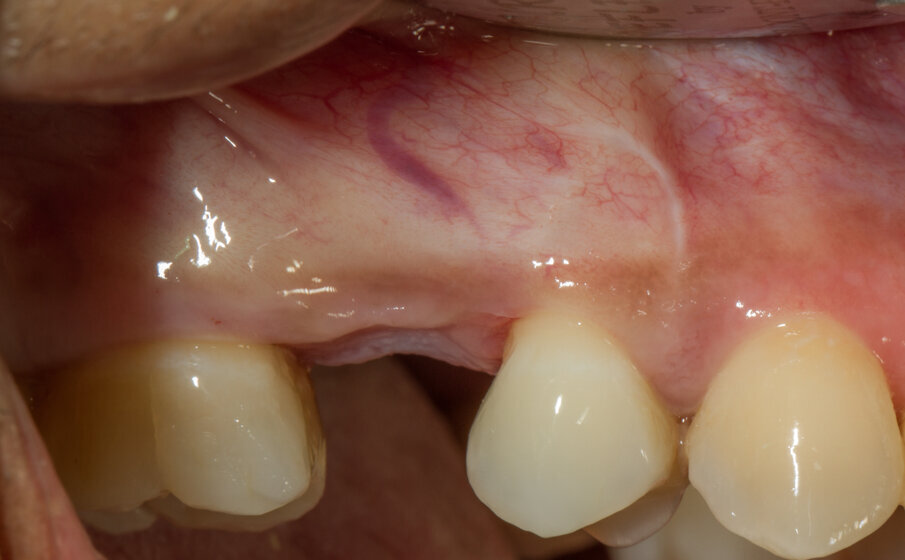

Viene inserito nel centro della cresta neoformata un impianto osteointegrato Neoss Tapered 4.0 x 13 mm con torque di inserimento di 60 Ncm e ISQ 80 (Figg. 22-24). La rigenerazione ossea crestale permette di inserire l’impianto in una posizione protesicamente guidata e con 2 mm di tessuto osseo vestibolare; questa situazione migliora la prevedibilità della riabilitazione implanto-protesica29-33. Dopo 2 mesi di provvisorizzazione si cementa il manufatto protesico definitivo (Figg. 25-28). Il controllo clinico e radiologico a 6 anni (Figg. 29, 30) mostra la stabilità dei tessuti molli e dell’osso perimplantare. Il confronto tra baseline e 6 anni dalla riabilitazione protesica evidenzia la stabilità nel tempo della rigenerazione volumetrica crestale (Fig. 31).

Fig. 25 - Situazione tissutale dopo 2 mesi di provvisorizzazione.